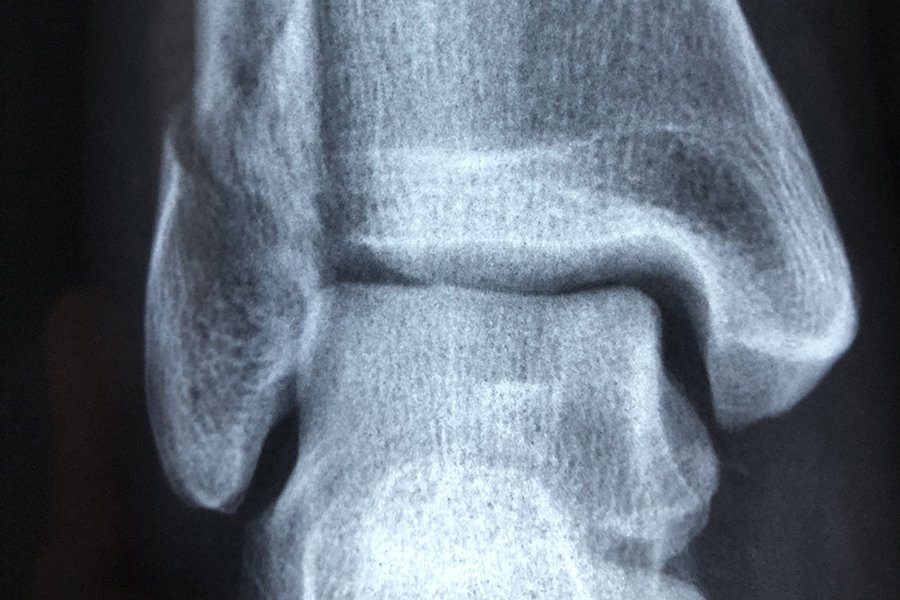

Форма коленной чашечки человека может быть индикатором того, подвержен ли он большему риску развития остеоартрита, согласно новому исследованию Австралийского национального университета (ANU). Исследование было опубликовано в журнале Osteoarthritis and Cartilage.

Команда, в которую вошли исследователи из ANU и больницы Канберры, собрала КТ-снимки у большой выборки здоровых людей и пациентов, ожидающих замены коленного сустава.

Используя передовые методы анализа изображений для создания 3D-моделей сотен костей коленной чашечки, команда затем применила методы моделирования формы для визуализации и измерения формы поверхностей коленной чашечки в трех измерениях.

Хотя они не нашли уникальных особенностей среди коленных чашечек женщин по сравнению с мужчинами, они обнаружили изменения в поверхностях коленной чашечки, которые были более выражены у людей с остеоартритом.

«Удивительно то, что различные суставные поверхности коленной чашечки по-разному меняют форму при остеоартрите и по мере увеличения тяжести заболевания», — сказала Уилсон.